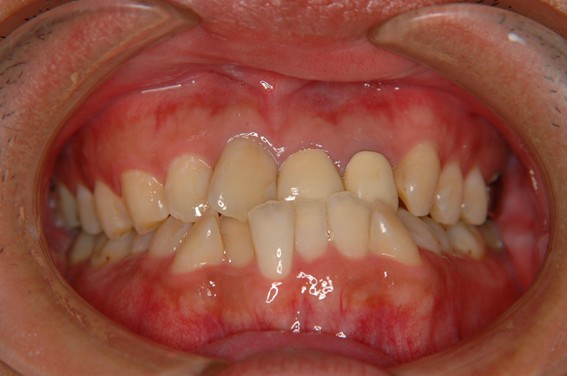

| 主訴 | 前歯が逆に噛んでいる。 |

| 治療内容 | 表側ワイヤー矯正、ジルコニア補綴を行いました。 |

| 治療費 | ワイヤー矯正660,000円(税込) ジルコニア176,000円(88,000円×2歯)(税込) |

| 治療期間 | 30ヶ月 |

| 治療回数 | 30回 |

| 想定されたリスク | 歯根吸収、歯髄壊死、歯髄充血、歯肉退縮のリスクがありました。 |

骨格性Ⅲ級・前歯部反対咬合の症例でした。反対咬合のまま治療していた前歯のサイズ不調和を、表側ワイヤー矯正とプロビジョナルクラウンで調整。正中を整え、犬歯・臼歯ともⅠ級、適切なオーバージェット(上下前歯の前後的な距離)・オーバーバイト(上下前歯の垂直的な重なり)に仕上げました。